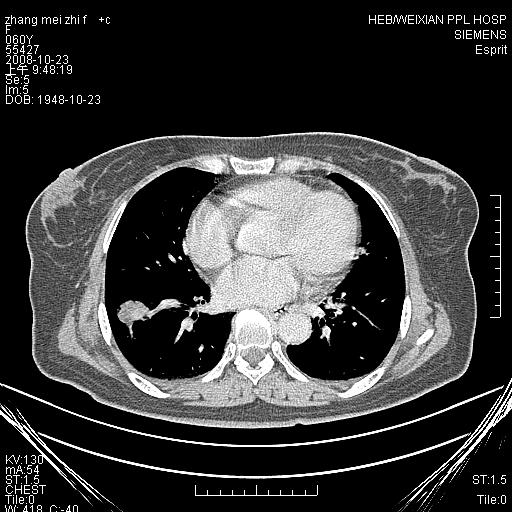

体检发现肺部肿块,现无不适。五年前曾有过哮喘病史。

强化扫描后病灶几乎无增强,强化后的病灶看起来密度虽高,是我为了清晰改变了窗宽窗位。(有点弄巧呈拙)

先对现有的图象资料谈几点看法:病变位于右肺下叶前基底段,上部呈类圆形改变,分叶及毛刺征象不明显,下部呈不规则气腔改变,近肺门侧可见与一粗大血管相连,考虑为引流静脉影.其他肺叶相对正常所见.分析:该病灶良恶性均有可能.(现有资料来说).强化及穿刺活检有助鉴别.

考虑右肺下叶前基底段周围型肺癌可能性大。

右肺下叶前基底段占位性病变,不排除周围型肺癌可能,尽快手术为妙。